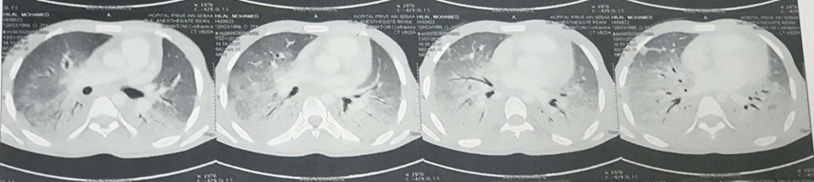

A chest CT scan was performed, revealing a diffuse bilateral ground-glass appearance, predominantly in the lower lobes, with confluent alveolar consolidation foci in the bilateral lower lobes, associated with adjacent peri-bronchovascular thickening (Figure 3).

Figure 3: Chest CT Scan on Day 7 of Treatment.